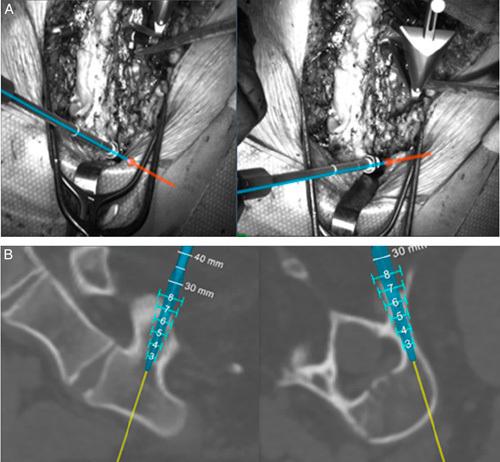

Intraoperative 2-dimensional (2D) fluoroscopy imaging has been commonly adopted for guidance during complex pediatric spinal deformity correction. Despite the benefits, fluoroscopy imaging emits harmful ionizing radiation, which has been well-established to have deleterious effects on the surgeon and operating room staff. This study investigated the difference in intraoperative fluoroscopy time and radiation exposure during pediatric spine surgery between 2D fluoroscopy-based navigation and a novel machine vision navigation system [machine vision image guidance system (MvIGS)].

This retrospective chart review was conducted at a pediatric hospital with patients who underwent posterior spinal fusion for spinal deformity correction from 2018 to 2021. Patient allocation to the navigation modality was determined by the date of their surgery and the date of implementation of the MvIGS. Both modalities were the standard of care. Intraoperative radiation exposure was collected from the fluoroscopy system reports.

A total of 1442 pedicle screws were placed in 77 children: 714 using MvIGS and 728 using 2D fluoroscopy. There were no significant differences in the male-to-female ratio, age range, body mass index, distribution of spinal pathologies, number of levels operated on, types of levels operated on, and the number of pedicle screws implanted. Total intraoperative fluoroscopy time was significantly reduced in cases utilizing MvIGS (18.6 ± 6.3 s) compared with 2D fluoroscopy (58.5 ± 19.0 s) ( P < 0.001). This represents a relative reduction of 68%. Intraoperative radiation dose area product and cumulative air kerma were reduced by 66% (0.69 ± 0.62 vs 2.0 ± 2.1 Gycm 2 , P < 0.001) and 66% (3.4 ± 3.2 vs 9.9 ± 10.5 mGy, P < 0.001) respectively. The length of stay displayed a decreasing trend with MVIGS, and the operative time was significantly reduced in MvIGS compared with 2D fluoroscopy for an average of 63.6 minutes (294.5 ± 15.5 vs 358.1 ± 60.6 min, P < 0.001).

In pediatric spinal deformity correction surgery, MvIGS was able to significantly reduce intraoperative fluoroscopy time, intraoperative radiation exposure, and total surgical time, compared with traditional fluoroscopy methods. MvIGS reduced the operative time by 63.6 minutes and reduced intraoperative radiation exposure by 66%, which may play an important role in reducing the risks to the surgeon and operating room staff associated with radiation in spinal surgery procedures.